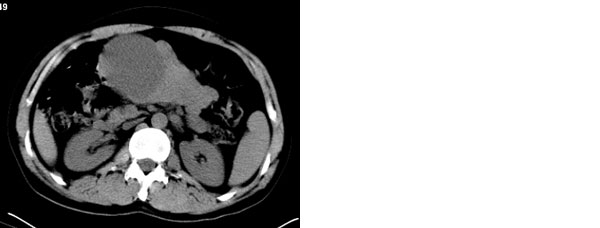

李**,男,46岁,便血1天入院,慢性贫血貌,腹平、软,剑突下压痛,肠鸣音稍活跃,hb大于1g/l,胃镜:慢性浅表性胃炎,b超:1肝内多发性占位 2腹腔内囊性肿块 ,肝内圆形影平扫ct值42.9,动脉期48.6,静脉期58.2,延迟期62.2

影像学表现:1 腹腔前中部、胰腺前方囊实性病灶(个人认为确定有否实性成分存在这是关键,涉及到鉴别诊断,如果是口服阳性造影剂则可明确左侧是不是小肠了),囊性部分囊壁不均,实性部分有强化,与小肠关系较密切,局部小肠受推移;与胰头、胃后壁均有脂肪间隙存在;2 胰腺无异常改变,胰周无渗出;3肝后段包膜下2个小圆形低密度灶,从图像和楼主提供的ct值来看有轻度强化,灶周无片状强化,不似单纯囊肿及肝癌、炎性病变表现;4 腹膜后及腹腔内无淋巴结肿大。

原因:胰头前方,前上腹部巨大囊实性肿物,与小肠关系密切,与胰头及胃壁之间脂肪间隙存在,囊壁不均匀,部分强化,占位效应明显,小肠上段扩张,十二指肠及胃腔内大量食物存留,说明上消化道有部分梗阻。因此,考虑来源于肠道的肿瘤。再结合其病史及肝内改变,这样考虑更有道理。

同意腹腔内囊实性恶性肿物伴肝内转移。